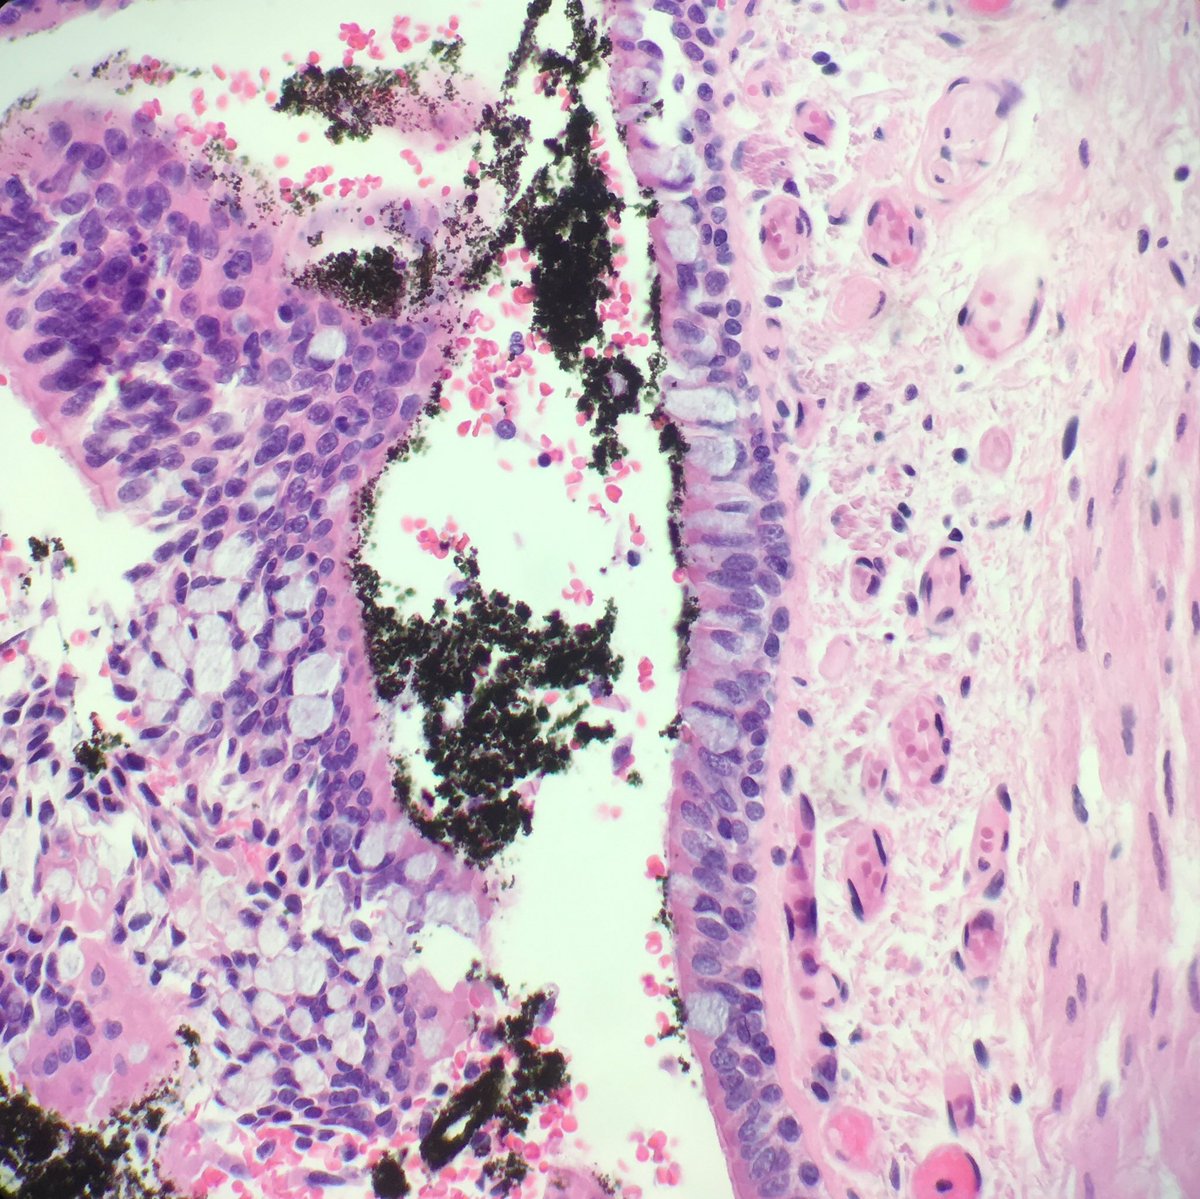

Fall from height: blunt force injuries including pulmonary contusions: interstitial and alveolar hemorrhage, damaged bronchioles and vessels with hemorrhage in the walls. Fat emboli can be seen (femoral shaft fracture x 2) #pulmonarypath #lungpath #forensics #forensicpath

seattlequinns's tweet image. Fall from height: blunt force injuries including pulmonary contusions: interstitial and alveolar hemorrhage, damaged bronchioles and vessels with hemorrhage in the walls. Fat emboli can be seen (femoral shaft fracture x 2) #pulmonarypath #lungpath #forensics #forensicpath